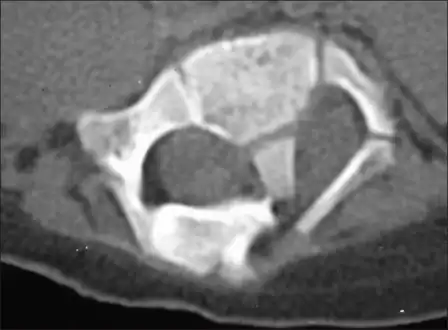

Adult presentation in diastematomyelia is unusual. With modern imaging techniques, various types of spinal dysraphism are being diagnosed in adults with increasing frequency. The commonest location of the lesion is at first to third lumbar vertebrae. Lumbosacral adult diastematomyelia is even rarer. Bony malformations and dysplasias are generally recognized on plain x-rays. MRI scanning is often the first choice of screening and diagnosis. MRI generally give adequate analysis of the spinal cord deformities although it has some limitations in giving detailed bone anatomy. Combined myelographic and post-myelographic CT scan is the most effective diagnostic tool in demonstrating the detailed bone, intradural and extradural pathological anatomy of the affected and adjacent spinal canal levels and of the bony spur.

Diastematomyelia usually occurs between 9th thoracic and 1st sacral levels of the spinal column with most being at the level of the upper lumbar vertebra. Cervical diastematomyelia is a very rare entity. The extent (or length of spinal cord involved) varies from one affected individual to another. In approximately 60% of patients with diastematomyelia, the two hemicords, each covered by an intact layer of pia arachnoid, travel through a single subarachnoid space surrounded by a single dural sac. Each hemicord has its own anterior spinal artery. This form of diastematomyelia is not accompanied by any bony spur or fibrous band and is rarely symptomatic unless hydromyelia or tethering is present. The other 40% of patients have a bony spur or a fibrous band that passes through the two hemicords. In these cases, the dura and arachnoid are split into two separate dural and arachnoidal sacs, each surrounding the corresponding hemicord which are not necessarily symmetric. Each hemicord contains a central canal, one dorsal horn (giving rise to a dorsal nerve root), and one ventral horn (giving rise to a ventral nerve root.) One study showed the bony spur typically situated at the most inferior aspect of the dural cleft. They advised that if the imaging appears to show otherwise, a second spur (present in about 5% of patients with diastematomyelia) is likely to be present.

Post-myelographic CT scanning provides individualized detailed maps that enable surgical treatment of cervical diastematomyelia, first performed in 1983.[1][2]